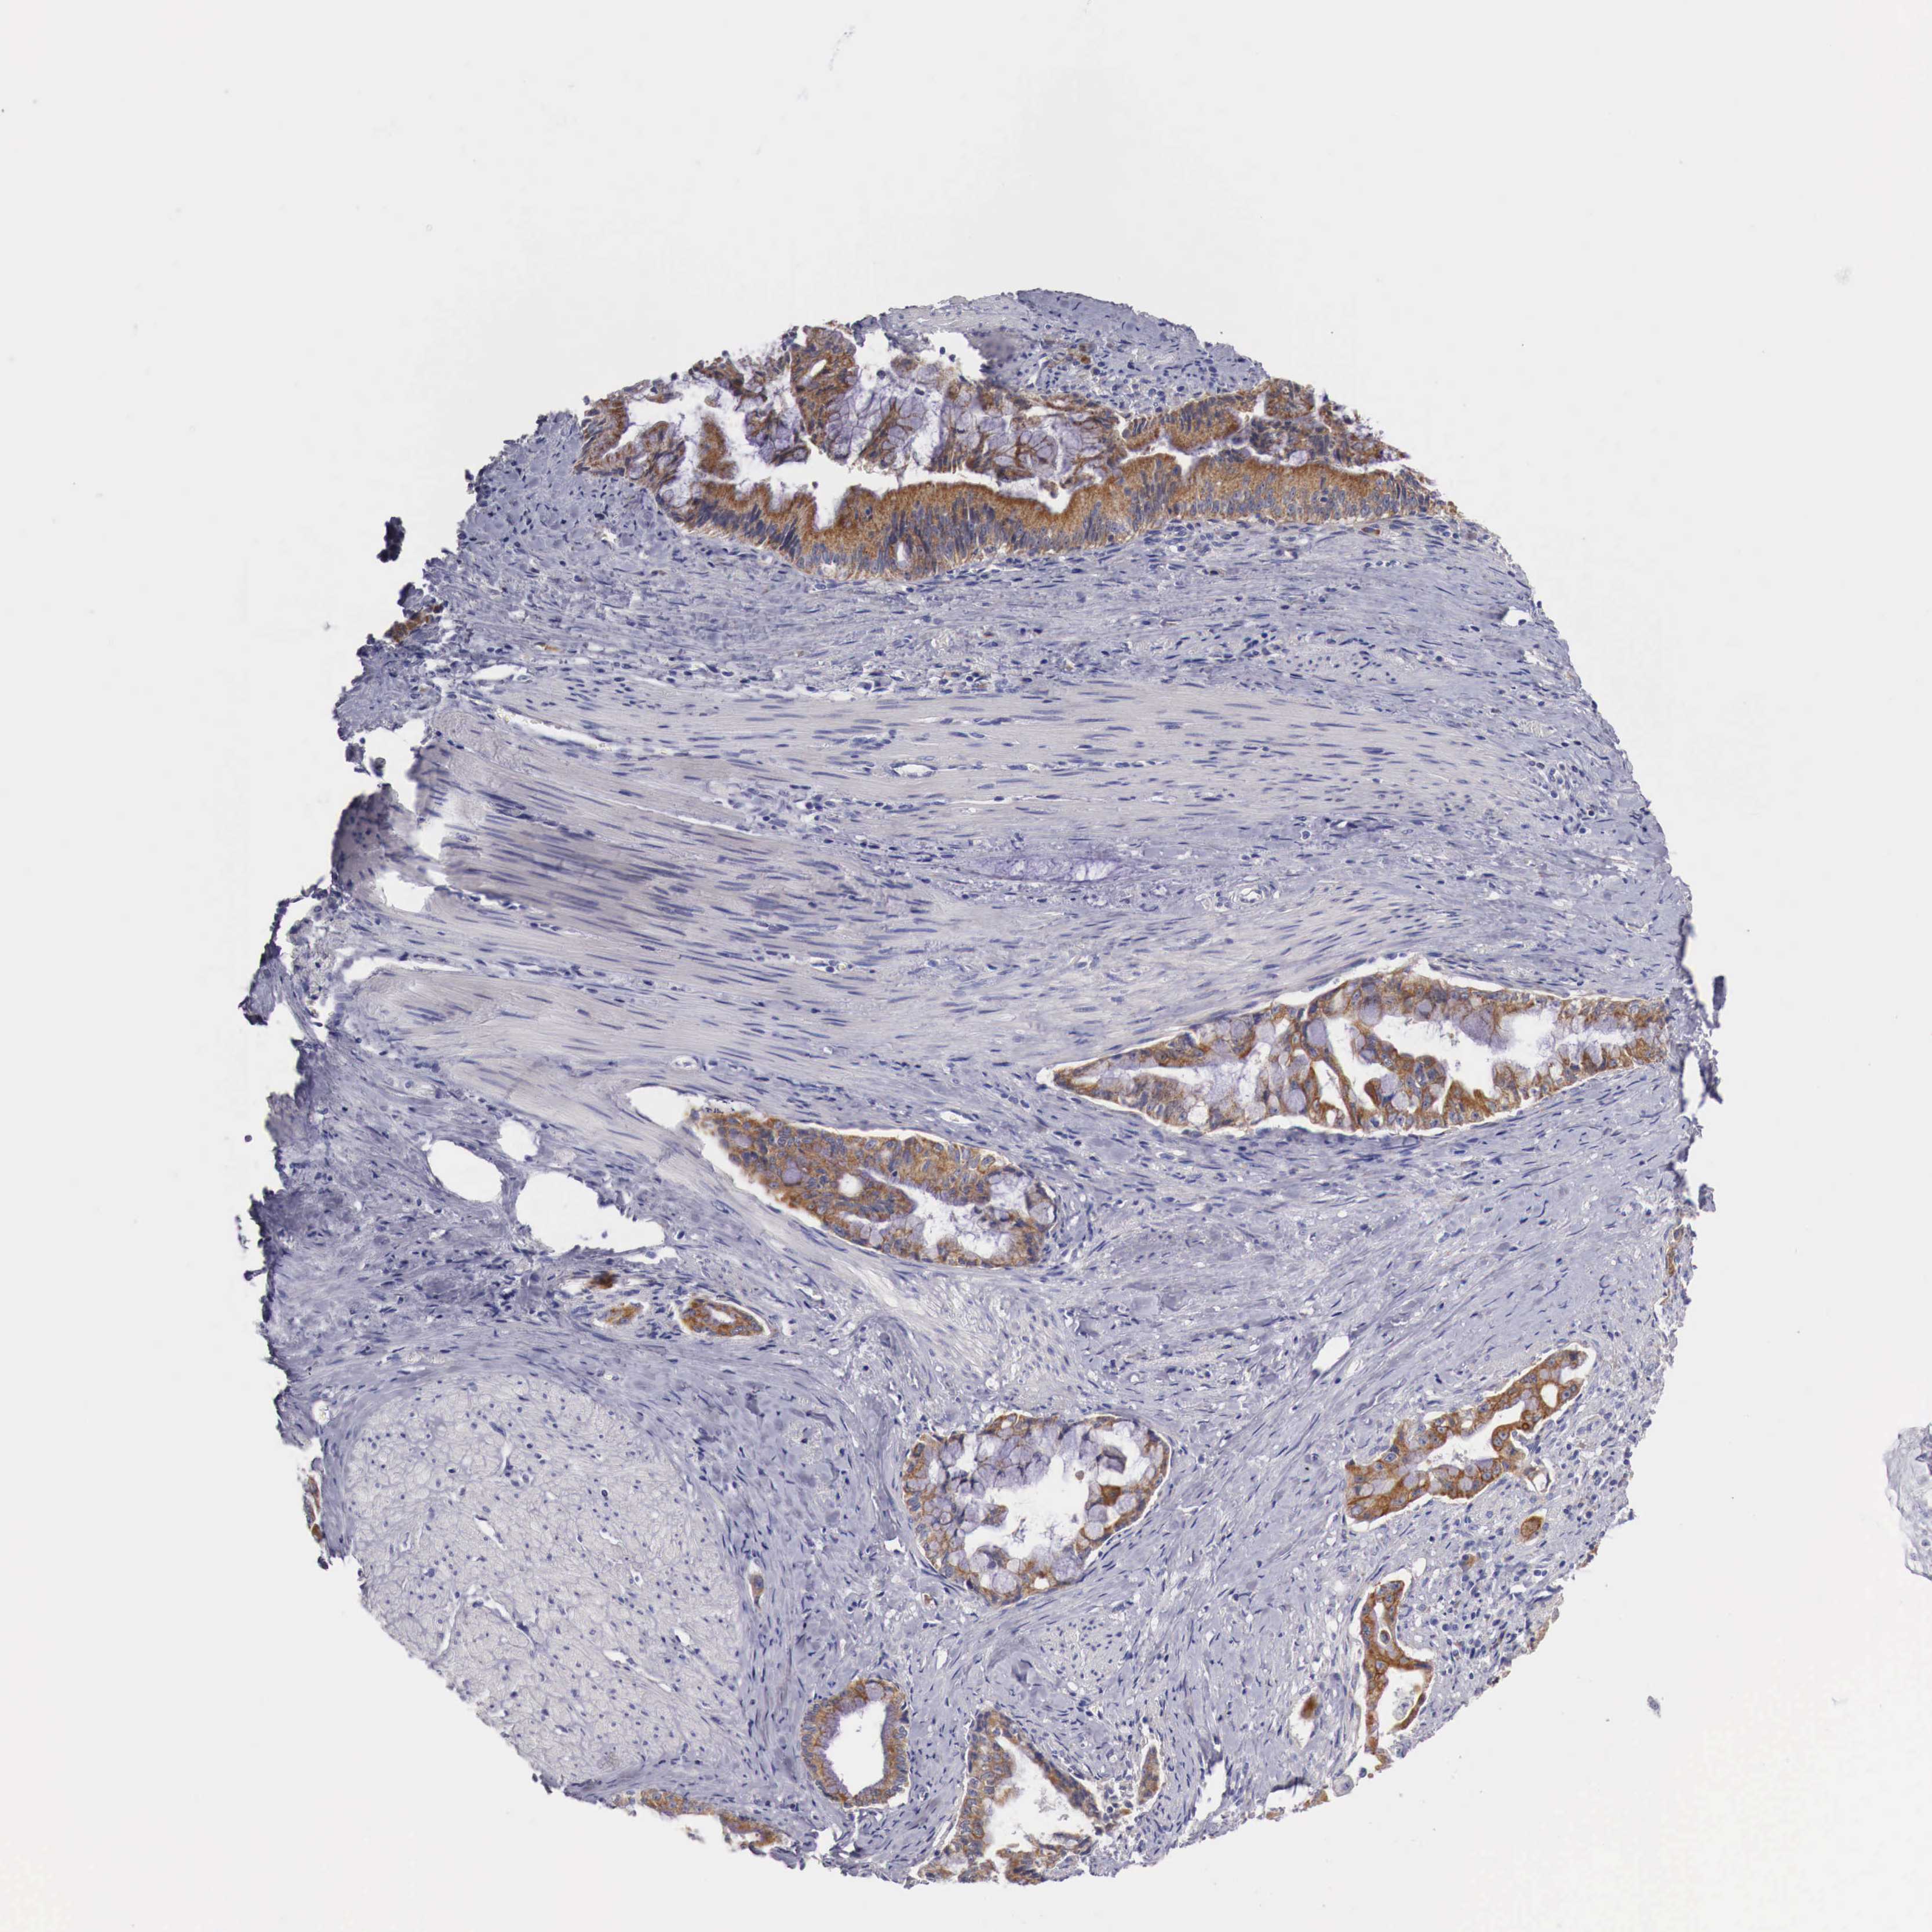

PANCREATIC CANCER - Protein expressioni

A mouse-over function shows sample information and annotation data. Click on an image to view it in a full screen mode. Samples can be filtered based on level of antibody staining by selecting one or several of the following categories: high, medium, low and not detected. The assay and annotation is described here.

Note that samples used for immunohistochemistry by the Human Protein Atlas do not correspond to samples in the TCGA dataset.

Antibody stainingi

Antibody staining in the annotated cell types in the current human tissue is reported as not detected, low, medium, or high, based on conventional immunohistochemistry profiling in selected tissues. This score is based on the combination of the staining intensity and fraction of stained cells.

Each image is clickable and will lead to virtual microscopy that enables deeper exploration of all samples and also displays staining intensity scores, fraction scores and subcellular localization as well as patient and tissue information for each sample.

Antibody HPA000545

Staining

High

Medium

Low

Not detected

Intensity

Strong

Moderate

Weak

Negative

Quantity

>75%

75%-25%

<25%

None

Location

Nuclear

Cytoplasmic/membranous

Cytoplasmic/membranous,nuclear

Adenocarcinoma, NOS